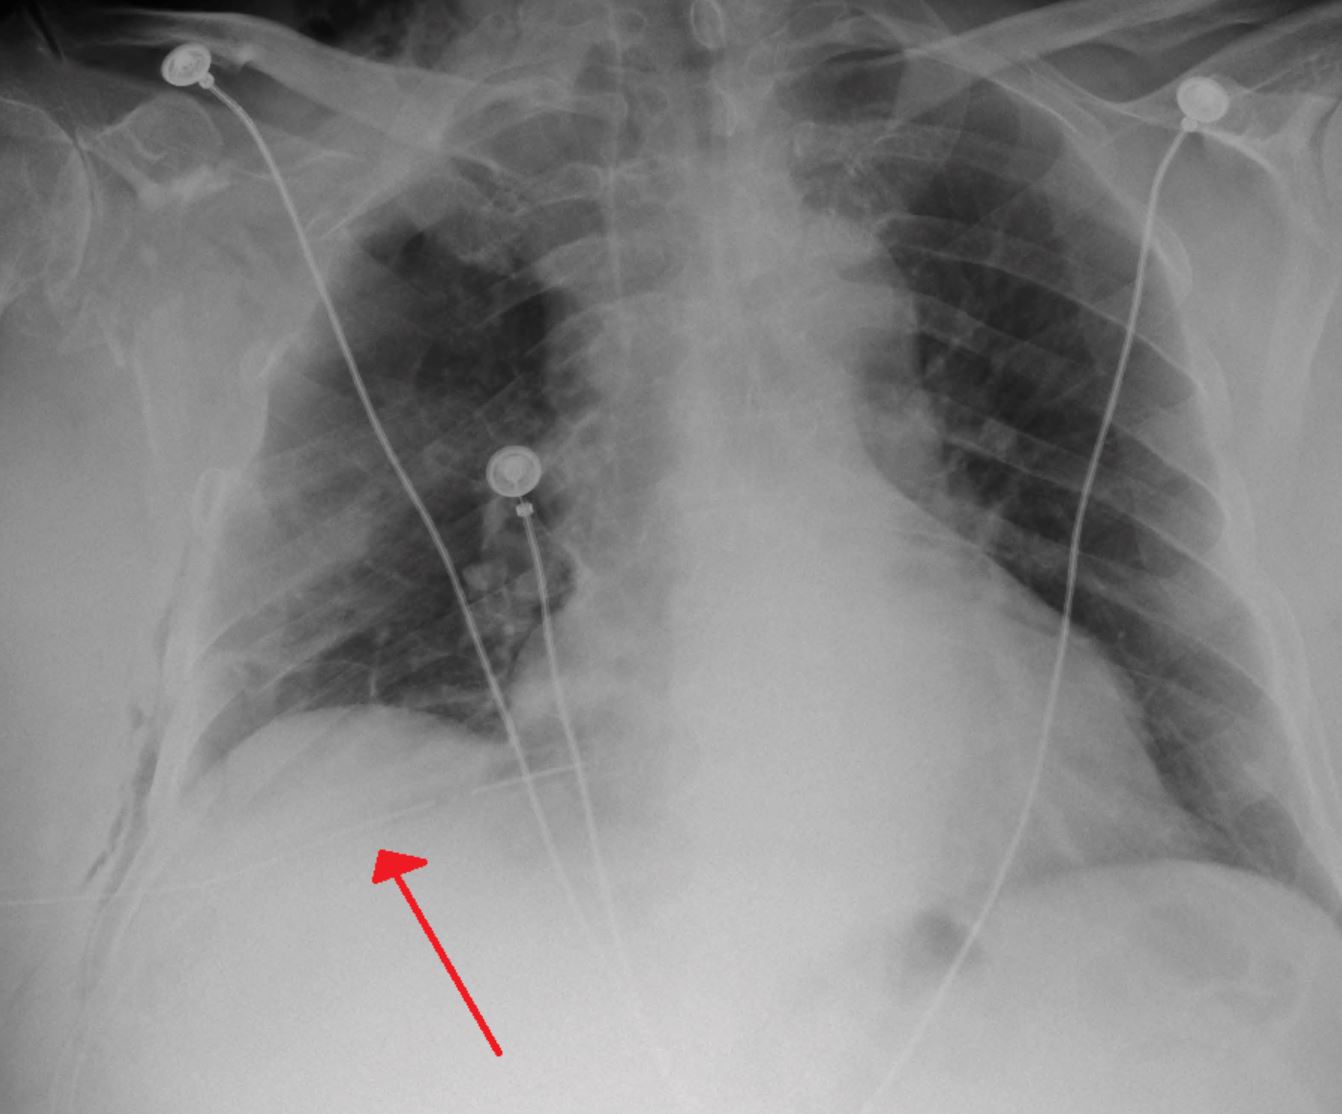

Setelah tiba di bilik kecemasan hospital tempatan, doktor mendiagnosnya mengalami pneumotoraks, juga dikenali sebagai "paru-paru runtuh".

Pneumotoraks merujuk kepada keadaan udara yang tidak normal di antara paru-paru dan dinding dada. Ia boleh disebabkan oleh pelbagai faktor seperti kecederaan dada, penyakit paru-paru, atau pecahnya alveolus disebabkan oleh tekanan yang tiba-tiba atau berlebihan.

Dalam kes ini, doktor percaya bahawa jeritan kuat lelaki muda tersebut semasa konsert menyebabkan pecahnya alveolus pada salah satu paru-parunya.

Nasib lelaki itu bagaimanapun baik apabila pasukan perubatan dengan pantas mengeluarkan udara berlebihan dari ruang pleura dan mengurangkan tekanan pada paru-parunya yang ‘runtuh’. Lelaki berusia 19 tahun itu juga dilaporkan dalam proses pemulihan yang baik.